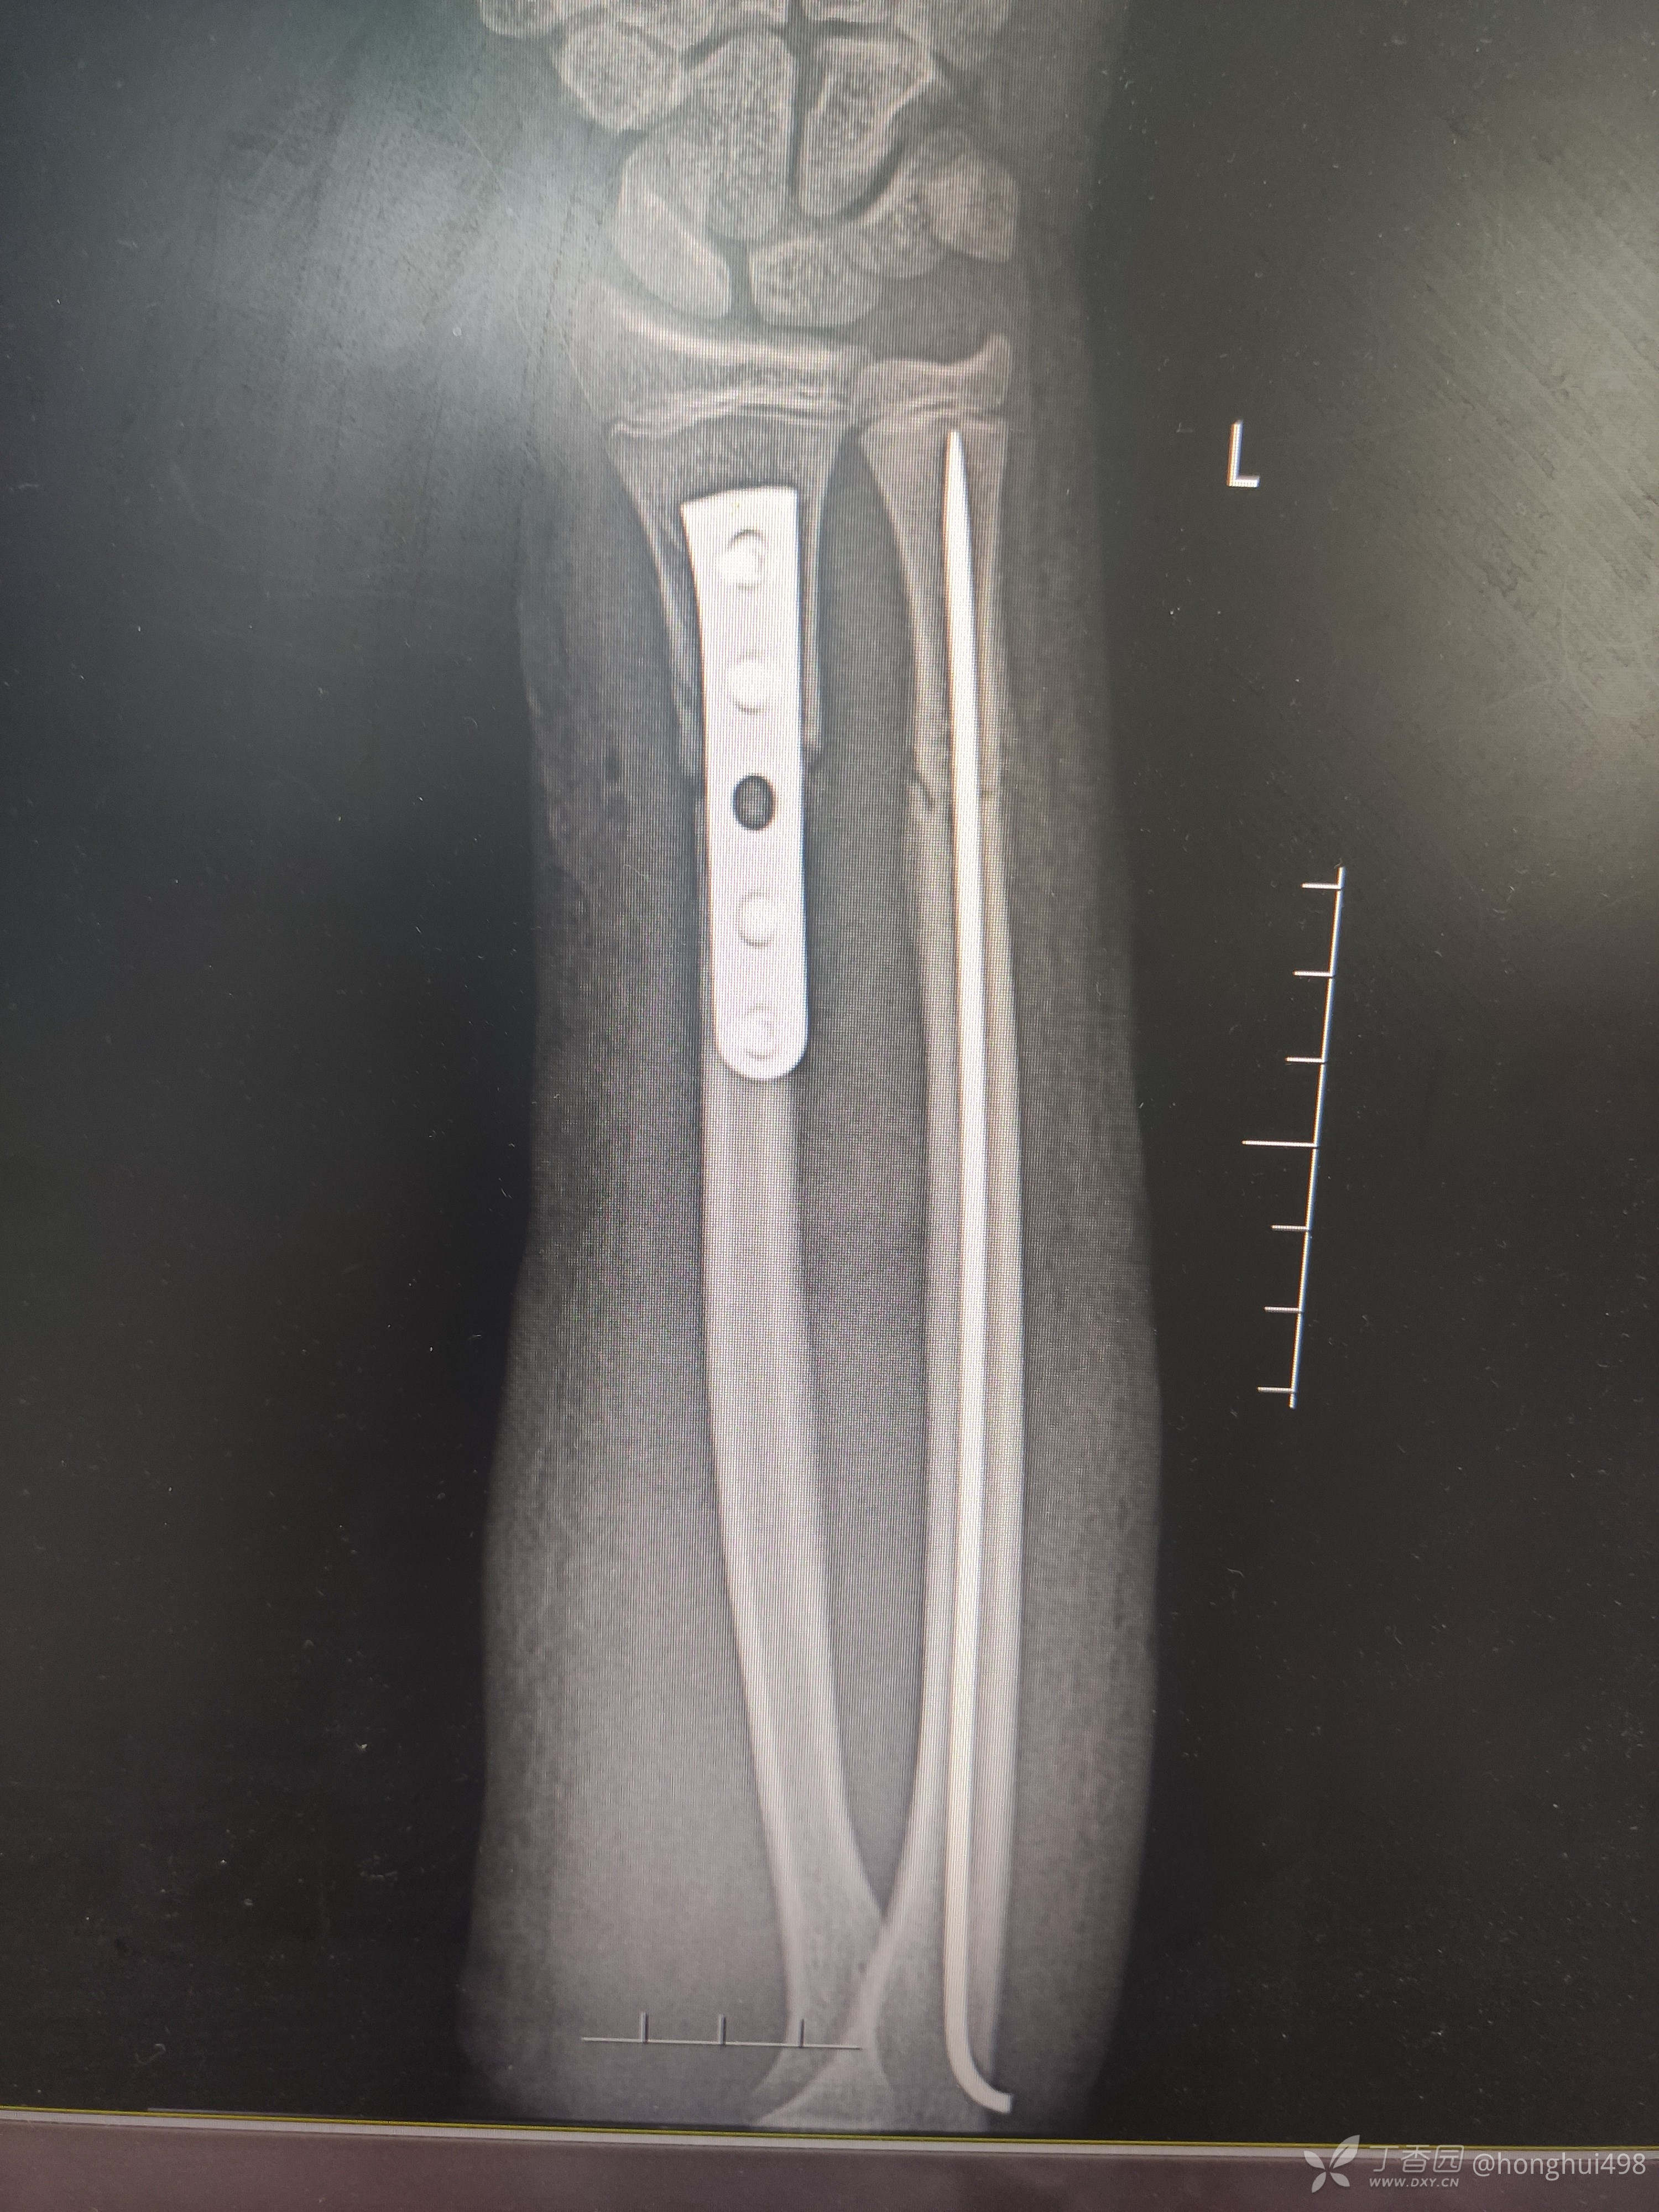

男性,14岁,摔倒致伤,左尺桡骨双骨折,肾病综合征。第一次受伤时手法整复,保守治疗两周后复查再次移位,二次入院手术治疗,术前计划桡骨闭合复位顺行髓内钉固定,术中发现复位不佳,切开复位钢板固定。